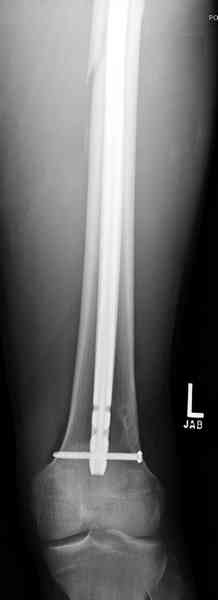

Несмотря на высокоэнергетический характер ранения, пуля не попала непосредственно в кость, а прошла рядом. Таким образом, для бедренной кости это ранение нельзя назватьв полном смысле этого слова высокоэнергетическим. К сожалению, не видно выходное отверстие. В любом случае, при таком переломе интрамедуллярный остеосинтез вполне показан. Кроме того, если пациент попал к Вам в первые часы после ранения, рана не должна рассматриваться как инфицированная. В качестве примера возможности даже более травматичной операции при таком характере перелома привожу следующий случай.

Пациент оперирован на 5-е сутки (переведен из другого лечебного учреждения)после сквозного пулевого ранения плеча и грудной клетки (непроникающее ранение той же пулей). Выполнен минимально инвазивный остеосинтез блокируемой метадиафизарной пластиной, повторная хирургическая обработка ран плеча. Заживление всех ран первичное, сращение наступило в обычные сроки.